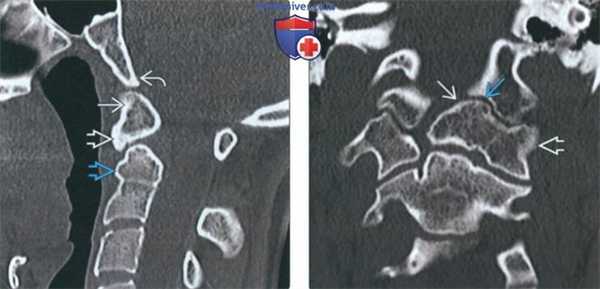

3. КТ при зубовидной кости:

• КТ в костном окне:

о Хорошо отграниченная кость на вершине зубовидного отростка + увеличение передней дуги С1

о Возможно слияние зубовидной кости со скатом или передней дугой С1

4. МРТ при зубовидной кости:

• Т1 ВИ:

о Обычный сигнал в губчатом веществе зубовидной кости, передней дуги С1

• Т2 ВИ:

о Картина аналогична Т1 ВИ:

о ± контузия спинного мозга, миеломаляция при краниоцервикальной нестабильности

(Слева) На сагиттальной КТ в костном окне определяется слияние дистопической зубовидной кости с передней дугой С1. Вершина ската минимально ремоделирована (уплощена). Определяется дисплазия короткого и округлого зубовидного отростка.

(Справа) На корональной КТ в костном окне определяется эксцентрическое слияние дистопической зубовидной кости с передней дугой и боковой массой С1 слева. Обратите также внимание на патологический псевдосустав между зубовидной костью и левым затылочным мыщелком.